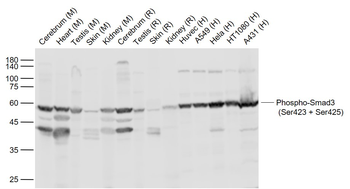

Phospho-Smad3 (Ser423 + Ser425) Rabbit Polyclonal Antibody [orb6983]

FC, IF, IHC-Fr, IHC-P, WB

Bovine, Canine, Equine, Gallus

Human, Mouse, Porcine, Rat

Rabbit

Polyclonal

Unconjugated

100 μl, 200 μl, 50 μlPhospho-SMAD5 (Ser463 + Ser465) Recombinant Rabbit Monoclonal Antibody [orb559123]